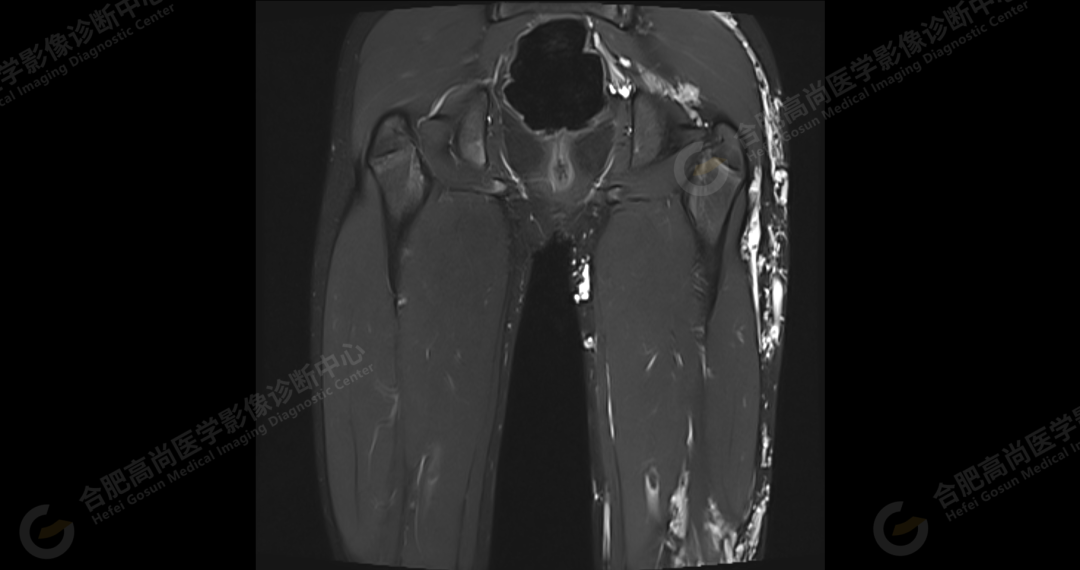

左侧髂骨内侧及闭孔内肌前方可见网格状异常信号影,边界欠清,T1WI 呈低信号,T2 压脂呈高信号,病变连续,延伸至臀肌内;左侧臀肌间隙及皮下、左大腿后部肌肉群及皮下、左膝前外侧及腘窝皮下、左小腿后侧皮下累及比目鱼肌及内外侧腓肠肌、左内外踝皮下、左足背足底及左足肌间隙内可见大片状、结节状弥漫性异常信号影,形态不规则,分布不均匀,边界不清,T1WI 呈低信号,T2WI 压脂后病灶呈高信号,部分病灶内可见网格状低信号,左足部肌间隙增宽,第 2-4 跖骨稍受压,骨质结构完整。左髋关节、膝、左踝关节间隙正常,无明显狭窄及增宽,关节面光滑,关节腔内无积液,左股骨、胫腓骨及踝部各组成骨骨质结构完整,未见明显异常改变。

左侧盆腔及下肢皮下及部分肌间隙内漫状血管瘤,请结合临床。